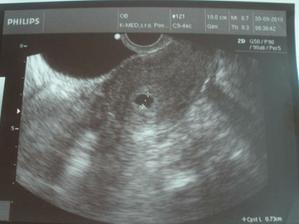

@monika0001 To je piaty týždeň aj tri dni.